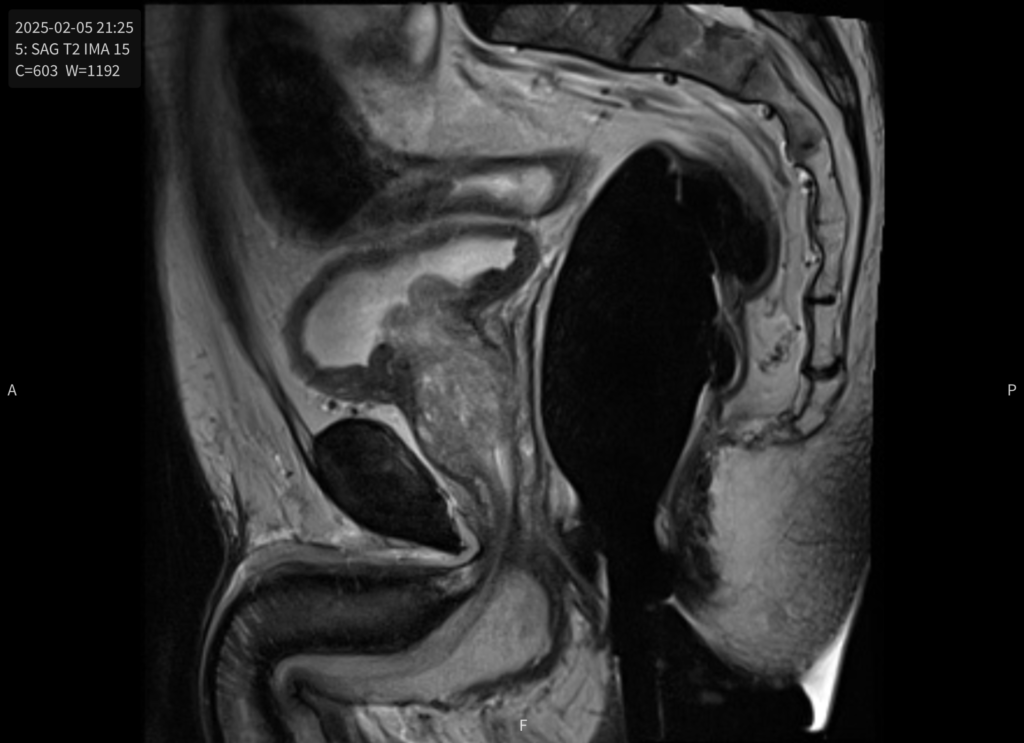

MRI – February 5th, 2025

Had the scheduled MRI – 9.30 at night. To be clear the MRI was scheduled as “MRI PROSTATE W ENDORECTAL COIL WWO CONT MULTIPARAMET PROST” another opportunity to lie on a table with some device inserted into your rectum! This is the first MRI I have ever had and, outside lasting for over an hour, the results where quite fascinating. The images are fantastic in that you can see all the muscle structures, organs, etc in extreme clarity and effectively sliced through your body. You can see the femur change at the ball of the hip, tail bones of the spine (Shoutout to Siemens Healthineers who were the manufacturer of the MRI machine – and part of the company I work for).

I picked out just a couple of images – not a doctor so I can’t be sure that what I am writing is accurate in any way at all.

More good news from the radiologist “No convincing tumor foci are identified.” which I guessed meant no indication of cancer but they could use some more encouraging language in other parts of their reports!